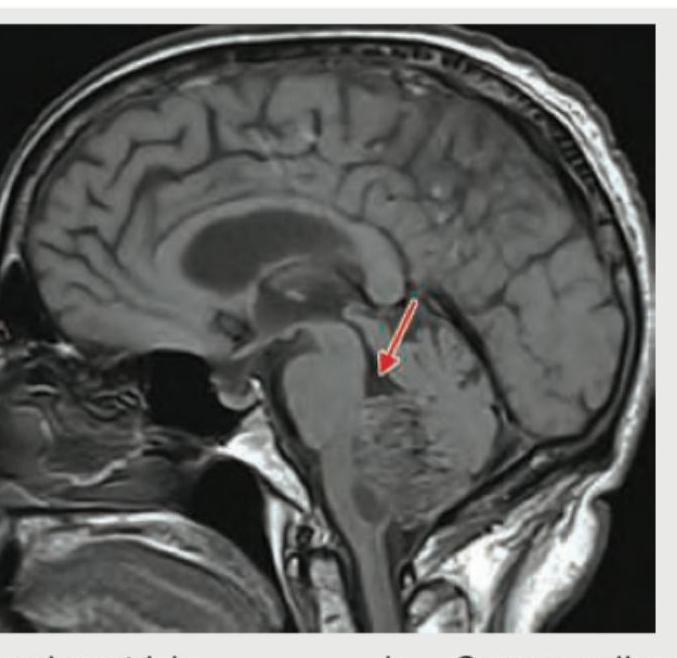

Explanation: ***3rd ventricle*** - The arrow points to a midline fluid-filled structure located superior to the **brainstem** and anterior to the **cerebellum** on this sagittal MRI image. - This anatomical position is characteristic of the **third ventricle**, which is a narrow cavity between the two thalami. *Lateral ventricle* - The **lateral ventricles** are much larger and are located more superiorly within the cerebral hemispheres, not in the midline position indicated. - They are connected to the third ventricle via the **foramina of Monro**. *Corpus callosum* - The **corpus callosum** is a thick band of white matter connecting the two cerebral hemispheres, located superior to the third ventricle. - It appears as a solid structure on MRI, not a fluid-filled space. *4th ventricle* - The **fourth ventricle** is located inferior to the third ventricle, anterior to the **cerebellum**, and posterior to the **pons** and **medulla**. - It leads into the central canal of the spinal cord and is distinctly inferior to the structure indicated by the arrow.